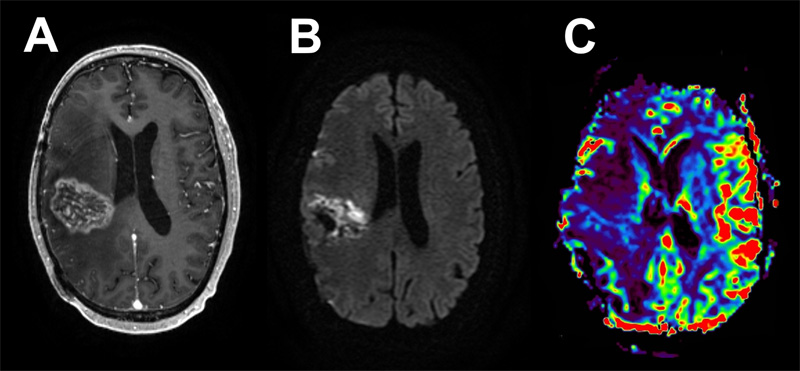

Figure 2: Case 1 Post-treatment imaging findings. An 8-month post-operative MRI following chemo-radiation showed evidence of pseudoprogression with significant associated cerebral edema. Axial T1 post-contrast (A) shows a heterogeneously enhancing, centrally necrotic mass, with restricted diffusion on DWI (B), and no associated hyperperfusion (C).

Five weeks later, the patient underwent a right temporo-parieto-occipital craniotomy for tumor resection. His postoperative course was complicated by a seizure upon awakening with right frontal venous infarct and layering remote cerebellar hemorrhage. He experienced weakness in his left upper and lower extremities and was discharged to a rehabilitation facility with antiepileptic and steroid medications. At 5 months follow-up, the patient had recovered his motor function with no additional seizures, was able to walk over a mile per day without assistance and was tolerating adjuvant chemoradiation. Subsequently, post-treatment MRIs demonstrated a heterogeneously enhancing, centrally necrotic mass in the right temporo-parietal tumor bed with no associated hyperperfusion, characteristic of evolving pseudoprogression. These findings were associated with marked hemispheric cerebral edema refractory to steroid treatment and requiring bevacizumab (Fig. 2).